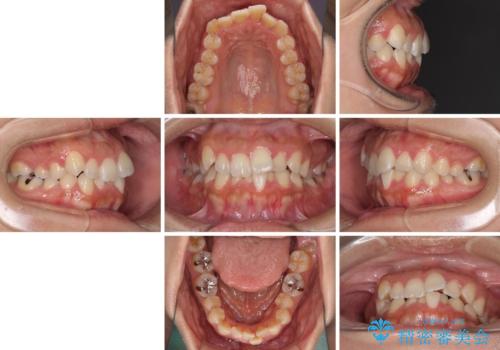

前歯のデコボコをインビザラインでスッキリと

- 上下前歯のデコボコを気にして来院された患者様です。

デコボコを解消する過程で、歯列の拡大により口元が突出する可能性があったため、4本の親知らずを抜歯しておき、歯列全体が後方に移動するように設計し、インビザラインにて矯正治療を行うこととしました。

日々の装着時間をしっかりと守って治療の臨んでくださったため、治療前のシミュレーションに近い形で矯正治療を進めて行くことができました。